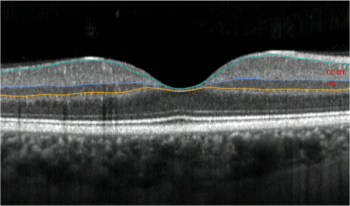

The investigators performed clinical examinations and obtained fundus photographs and inferior optical coherence tomography (OCT) images for both treatments at baseline and on days 1, 3, 8, 15, and 56 after the injections.

Optical coherence tomography analysis of measurements of cystoid macular lesions showed that patients with different IRD phenotypes can develop very large CMLs.